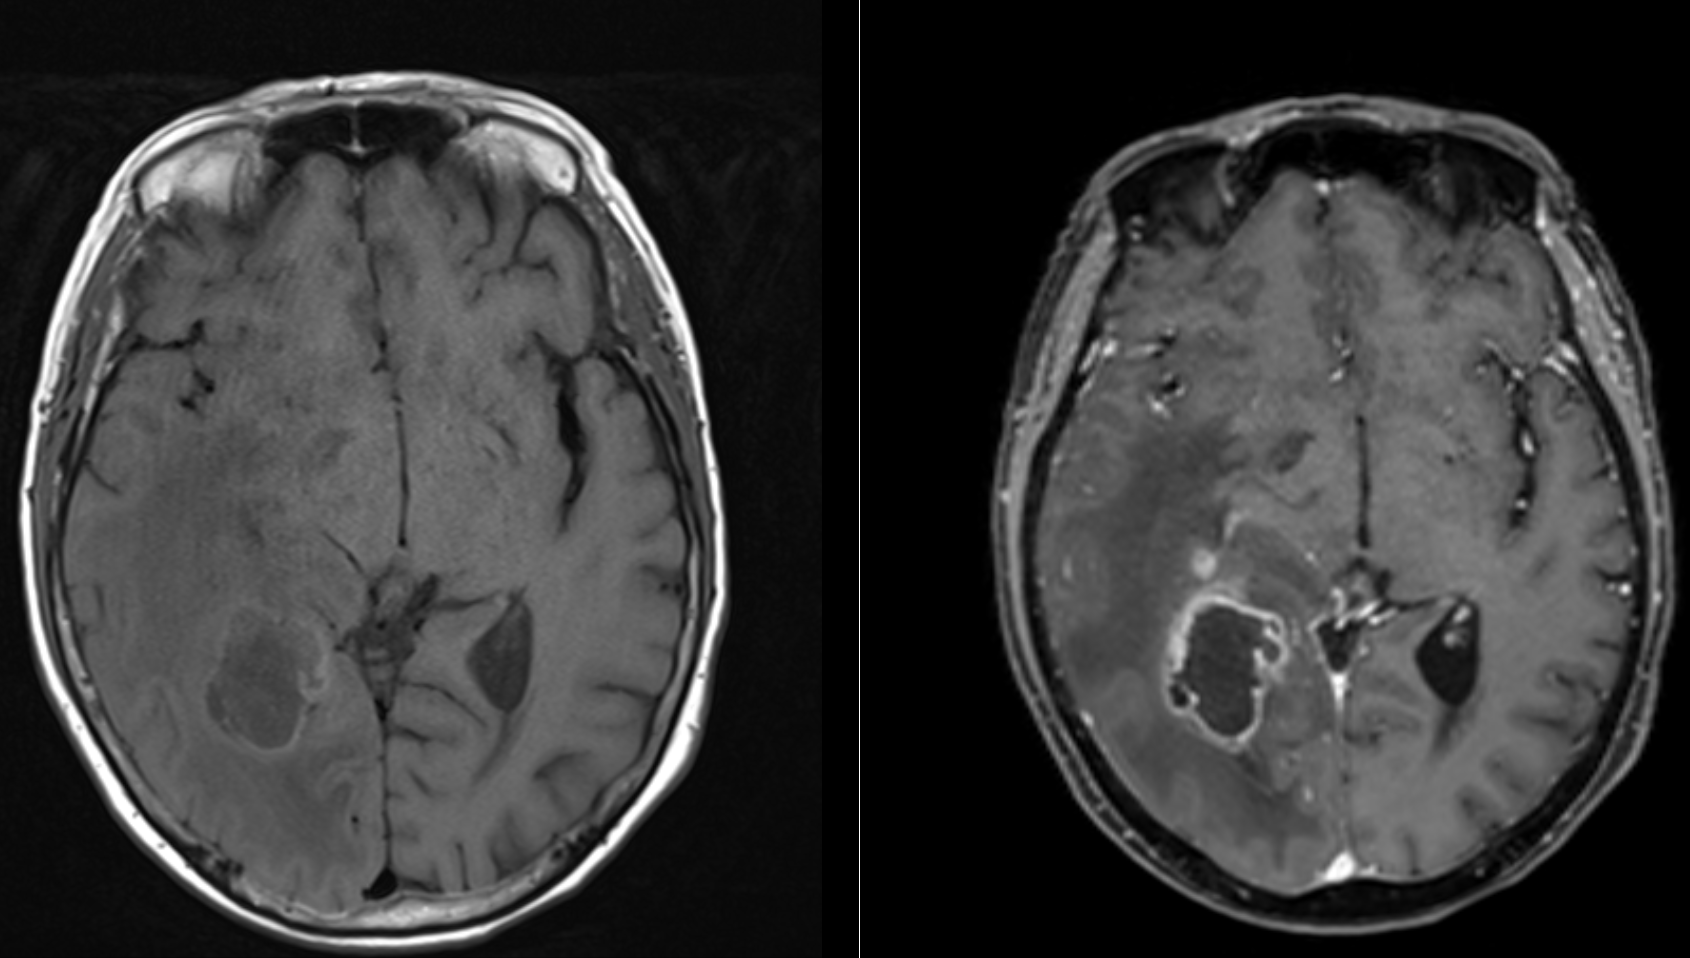

Ein Suchmaschinenoptimierungsexperiment für den Begriff Glioblastom

Mein kleines Nebenprojekt Ars Neurochirurgica ist eine Website mit verschiedenen Beiträgen und Informationen zu neurochirurgischen Themen und wurde im Jahr 2018 ins Leben gerufen. Erfreulicherweise kam es über die Zeit immer über einen kontinuierlichen Zuwachs an Besuchern. Ich werde versuchen eine Unterseite, welche sich ausführlich mit dem Krankheitsbild Glioblastom, einem aggressiven Hirntumor, beschäftigt in den Rankings nach oben zu bringen.